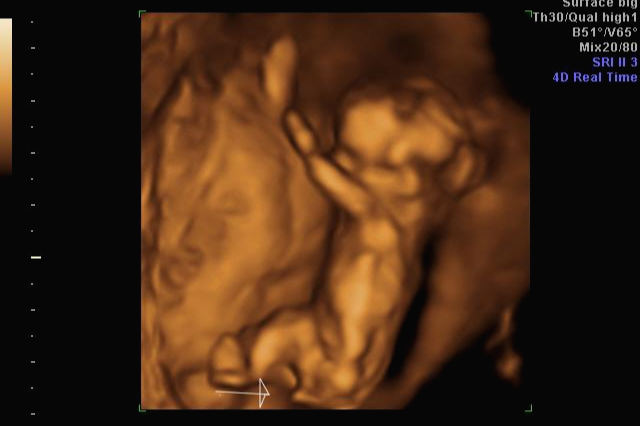

입체 초음파 사진은 항상 만족스러워요! 사진 보면 벌써 태어난 아기처럼 어찌 이리 이목구비 뚜렷하고 아이 얼굴이 선명하게 잘 보이는지~ 제아이라 이렇게 사랑스러운 걸까요~? ㅋㅋㅋ

내 뱃속에 이렇게 사랑스러운 아이가 있다니 >. < 이렇게 이쁜 아이를 보면 성별반전은 중요하지 않아요~